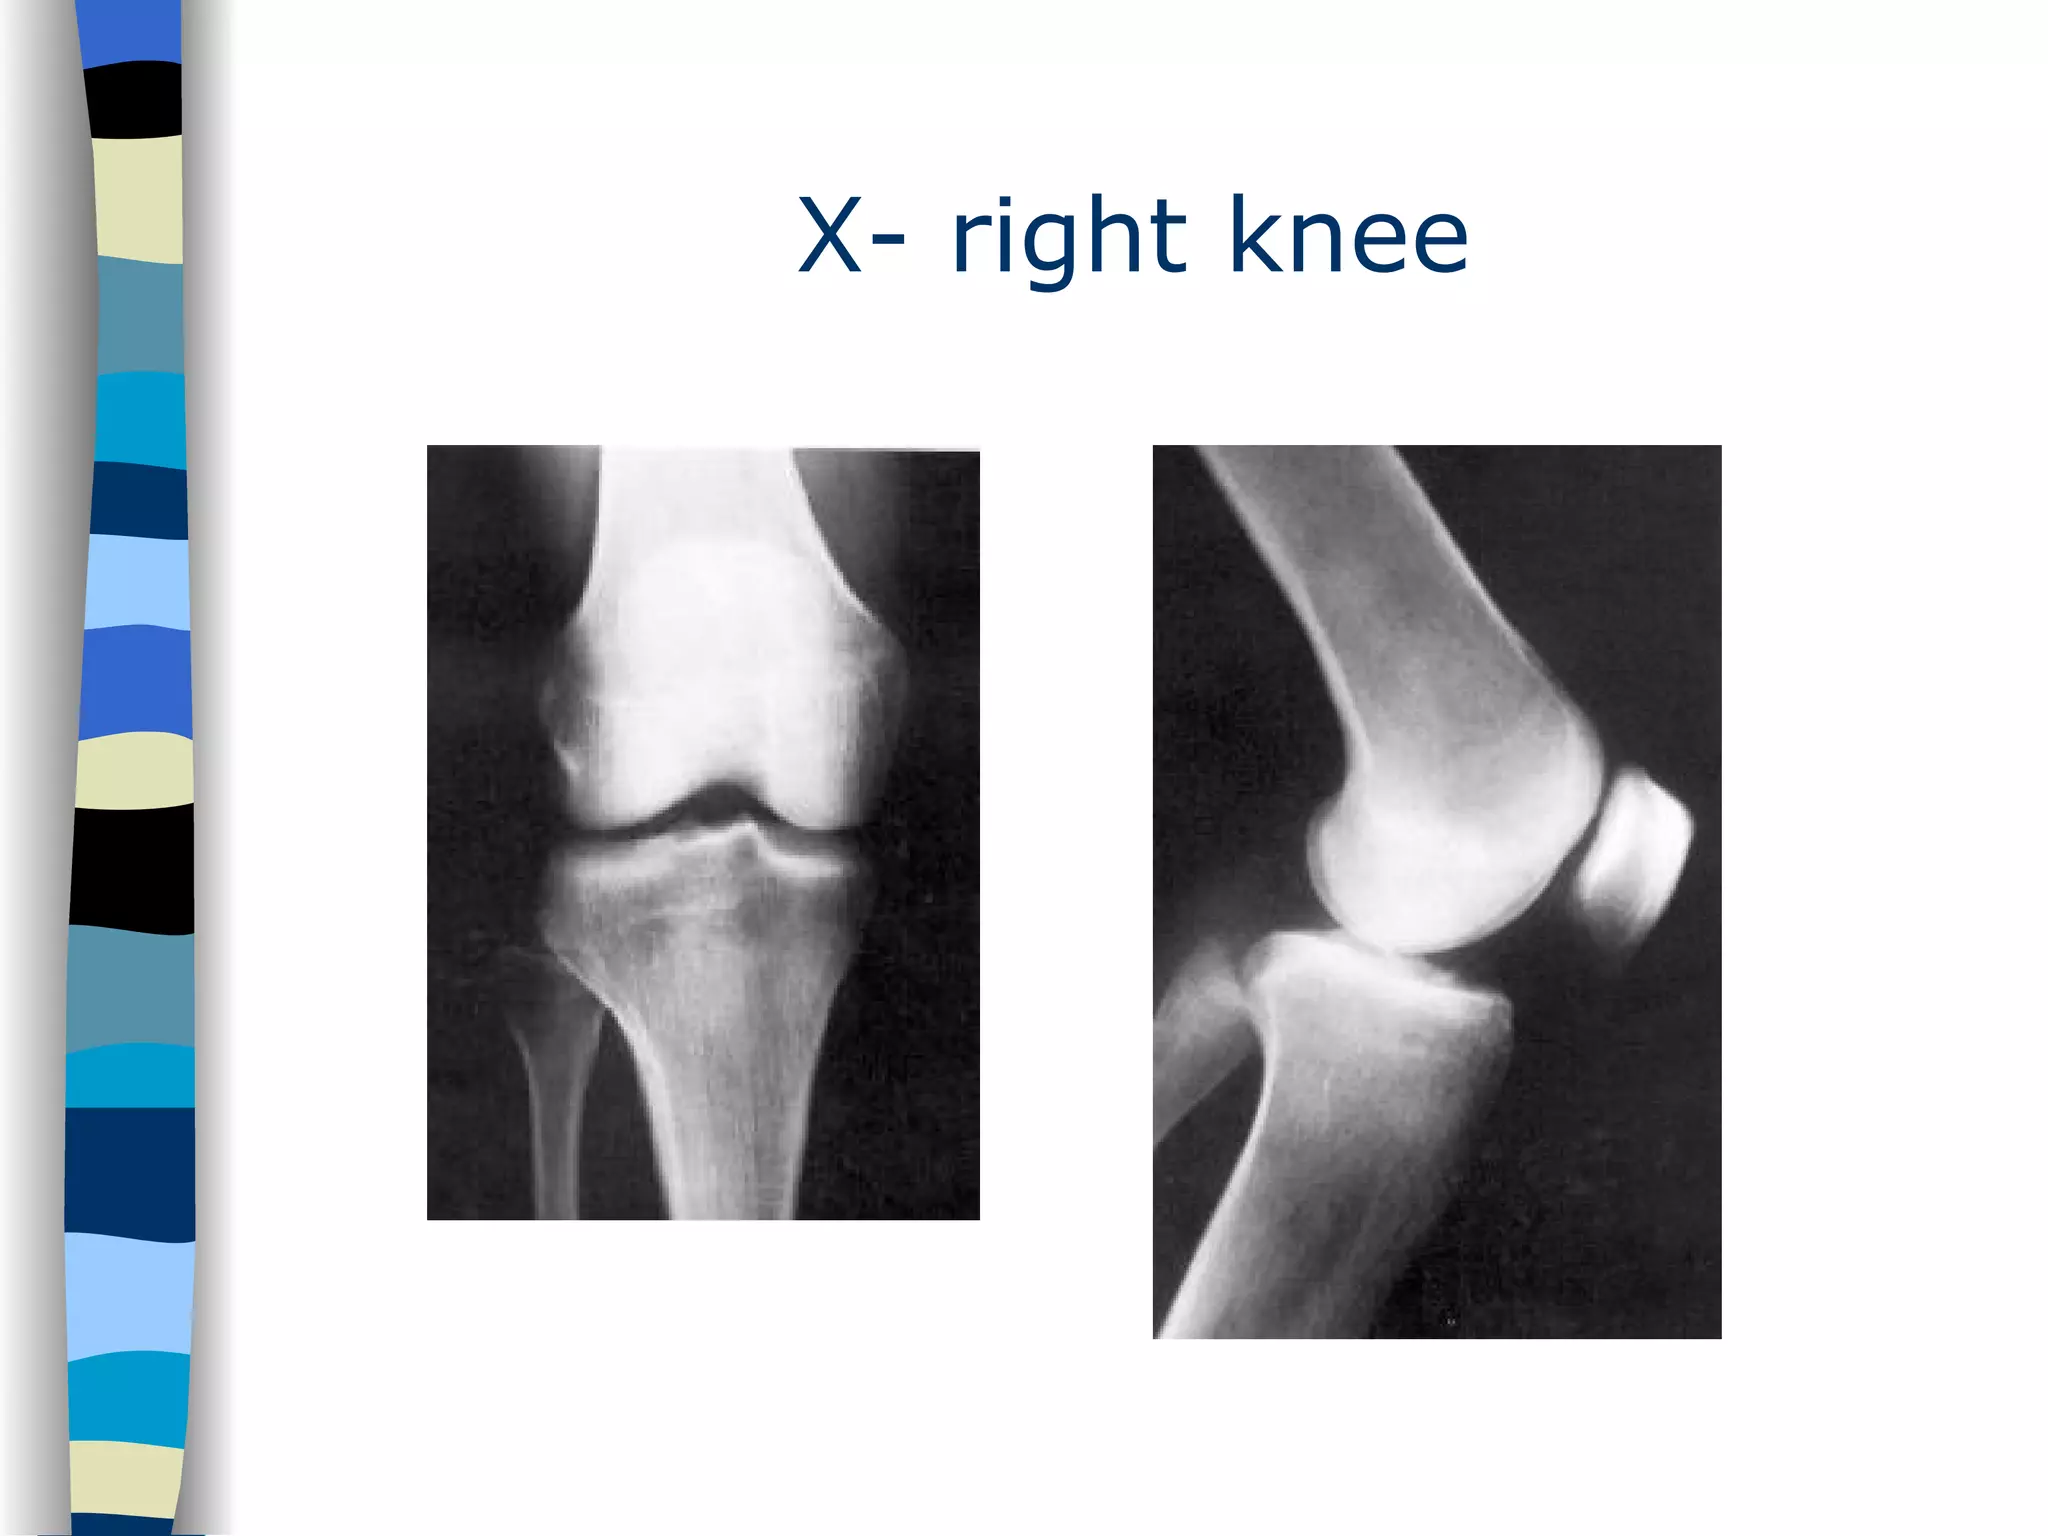

Clinical Case: Debby A 17 year old girl is brought into the ER after a scooter accident. She was shortly unconscious  at the scene. She complaints of headache and a painful right knee

X- right knee

In the meantime… While waiting for the X- ray of the right knee patient starts to vomit. She also complaints of enormous headache. What will you do now?